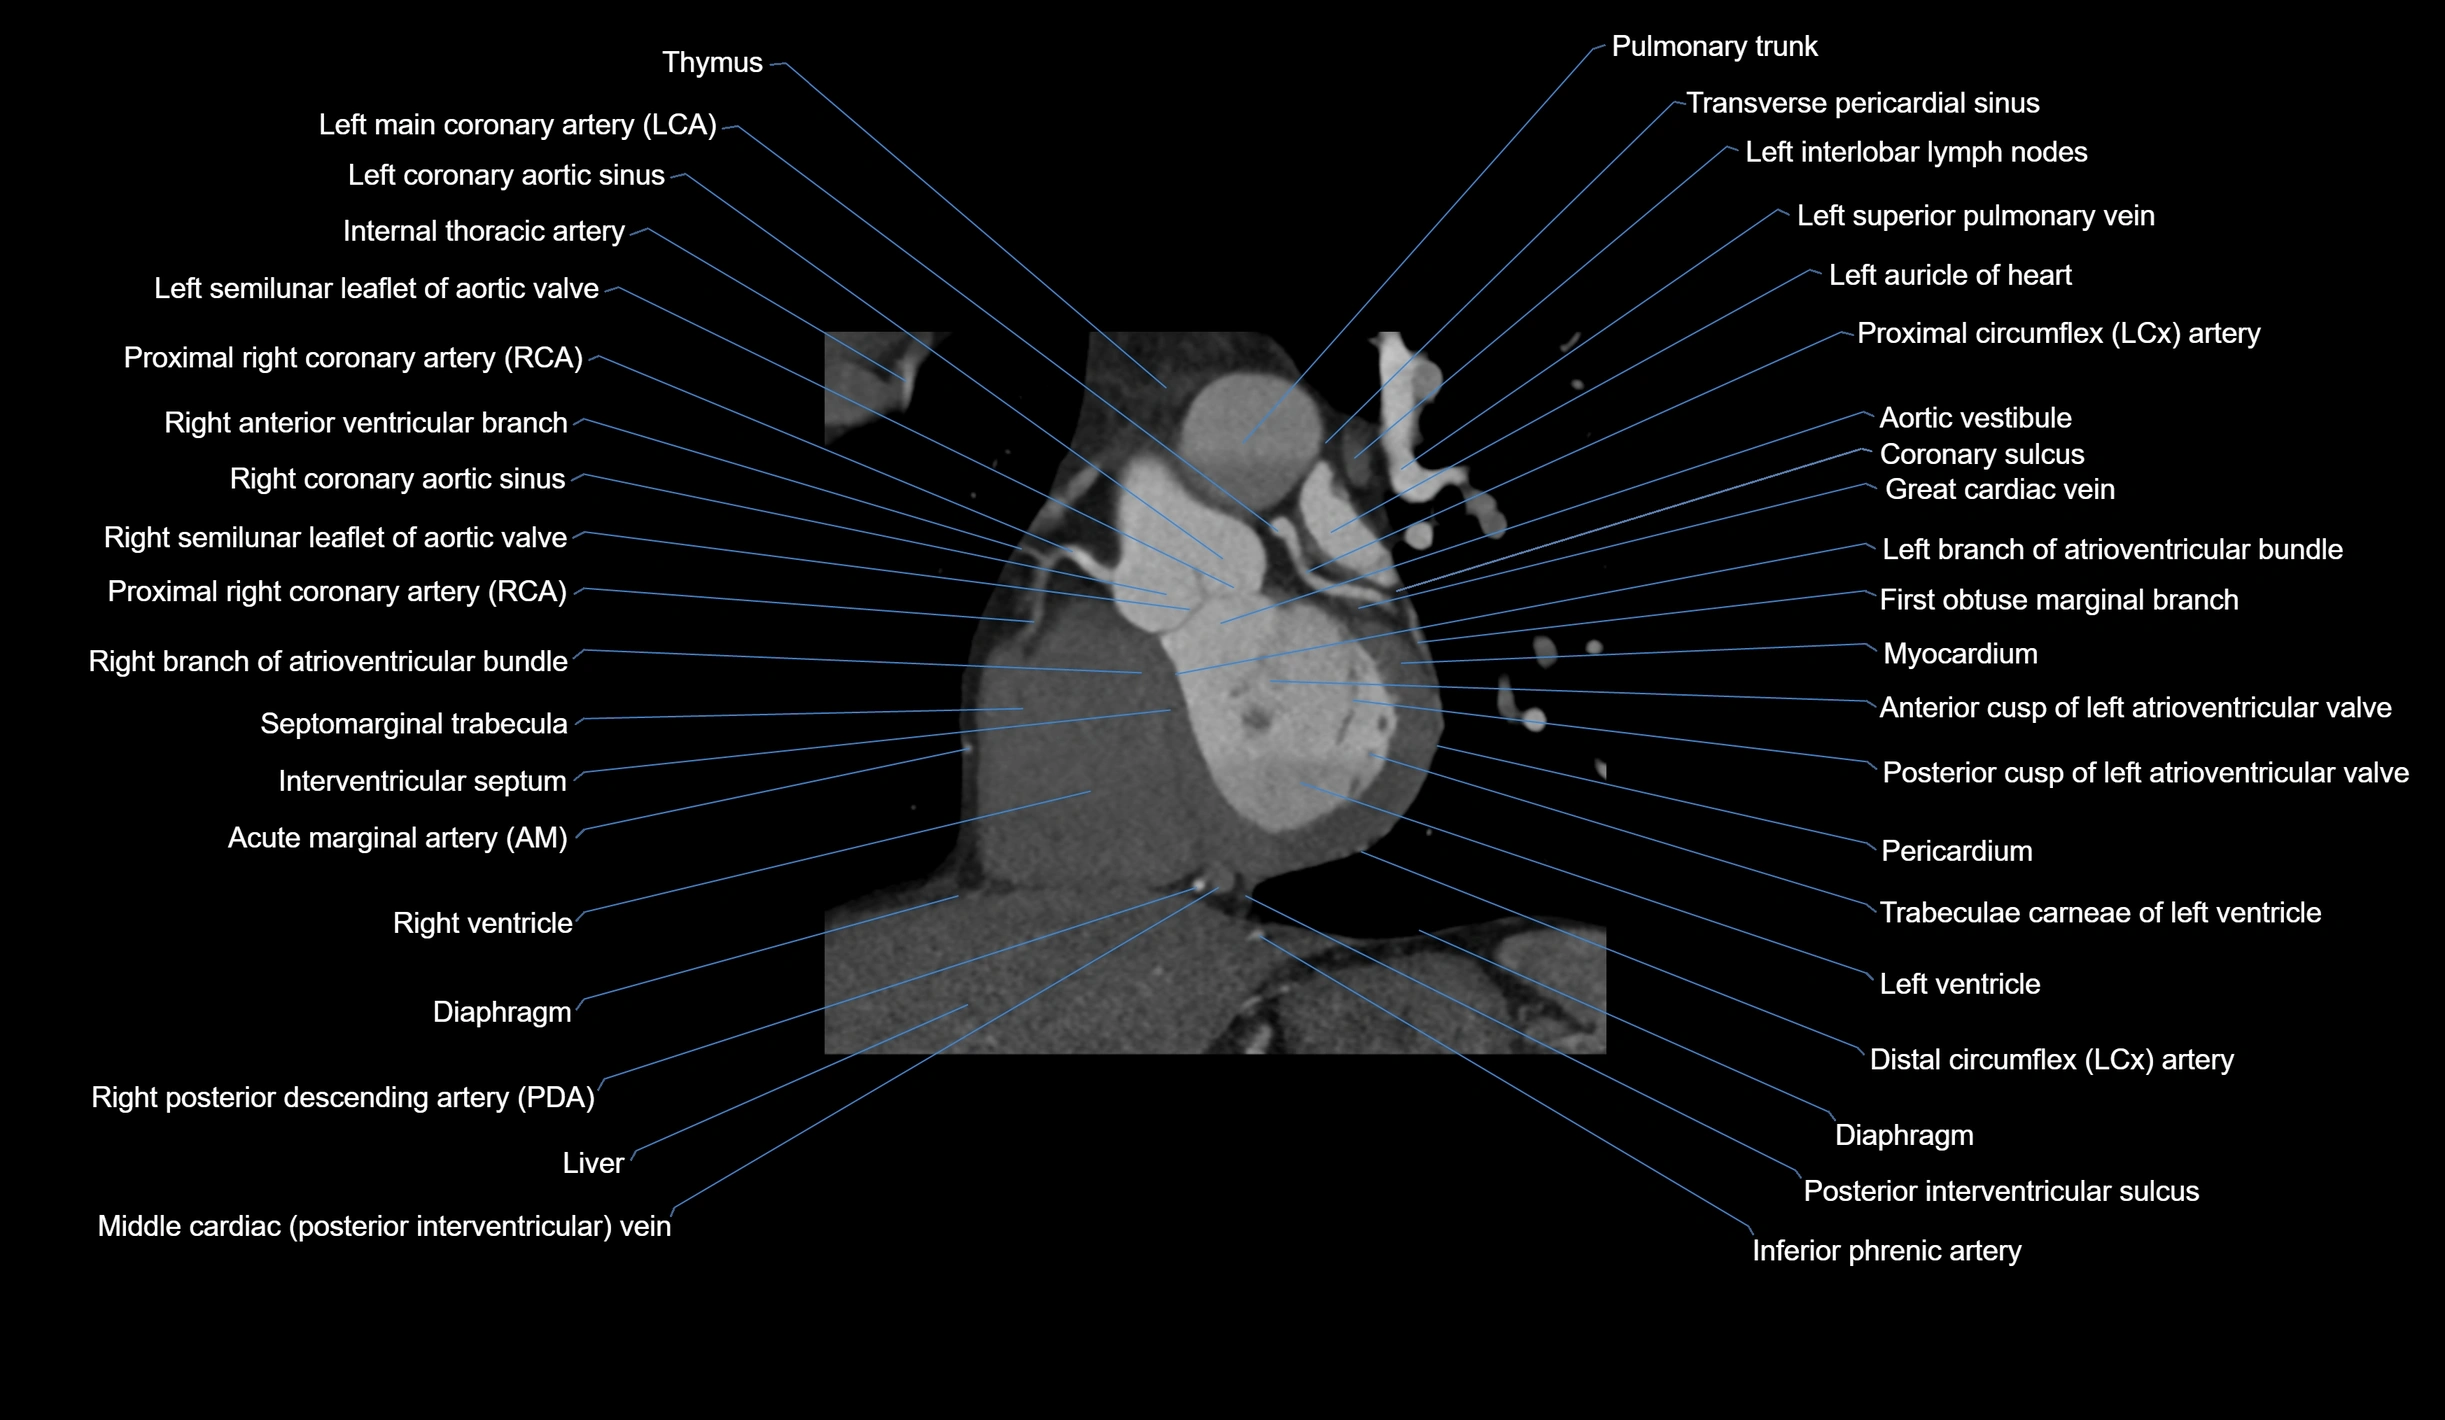

CT images